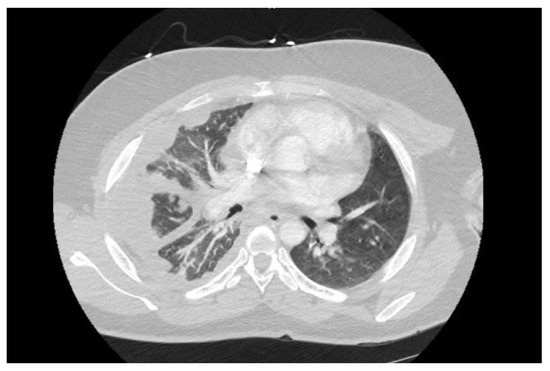

Introduction: Hypertension is occasionally associated with congenital hydronephrosis. Case report: The authors report a four-month-old boy with severe left congenital hydronephrosis and transient hypertension triggered by his first urinary tract infe...